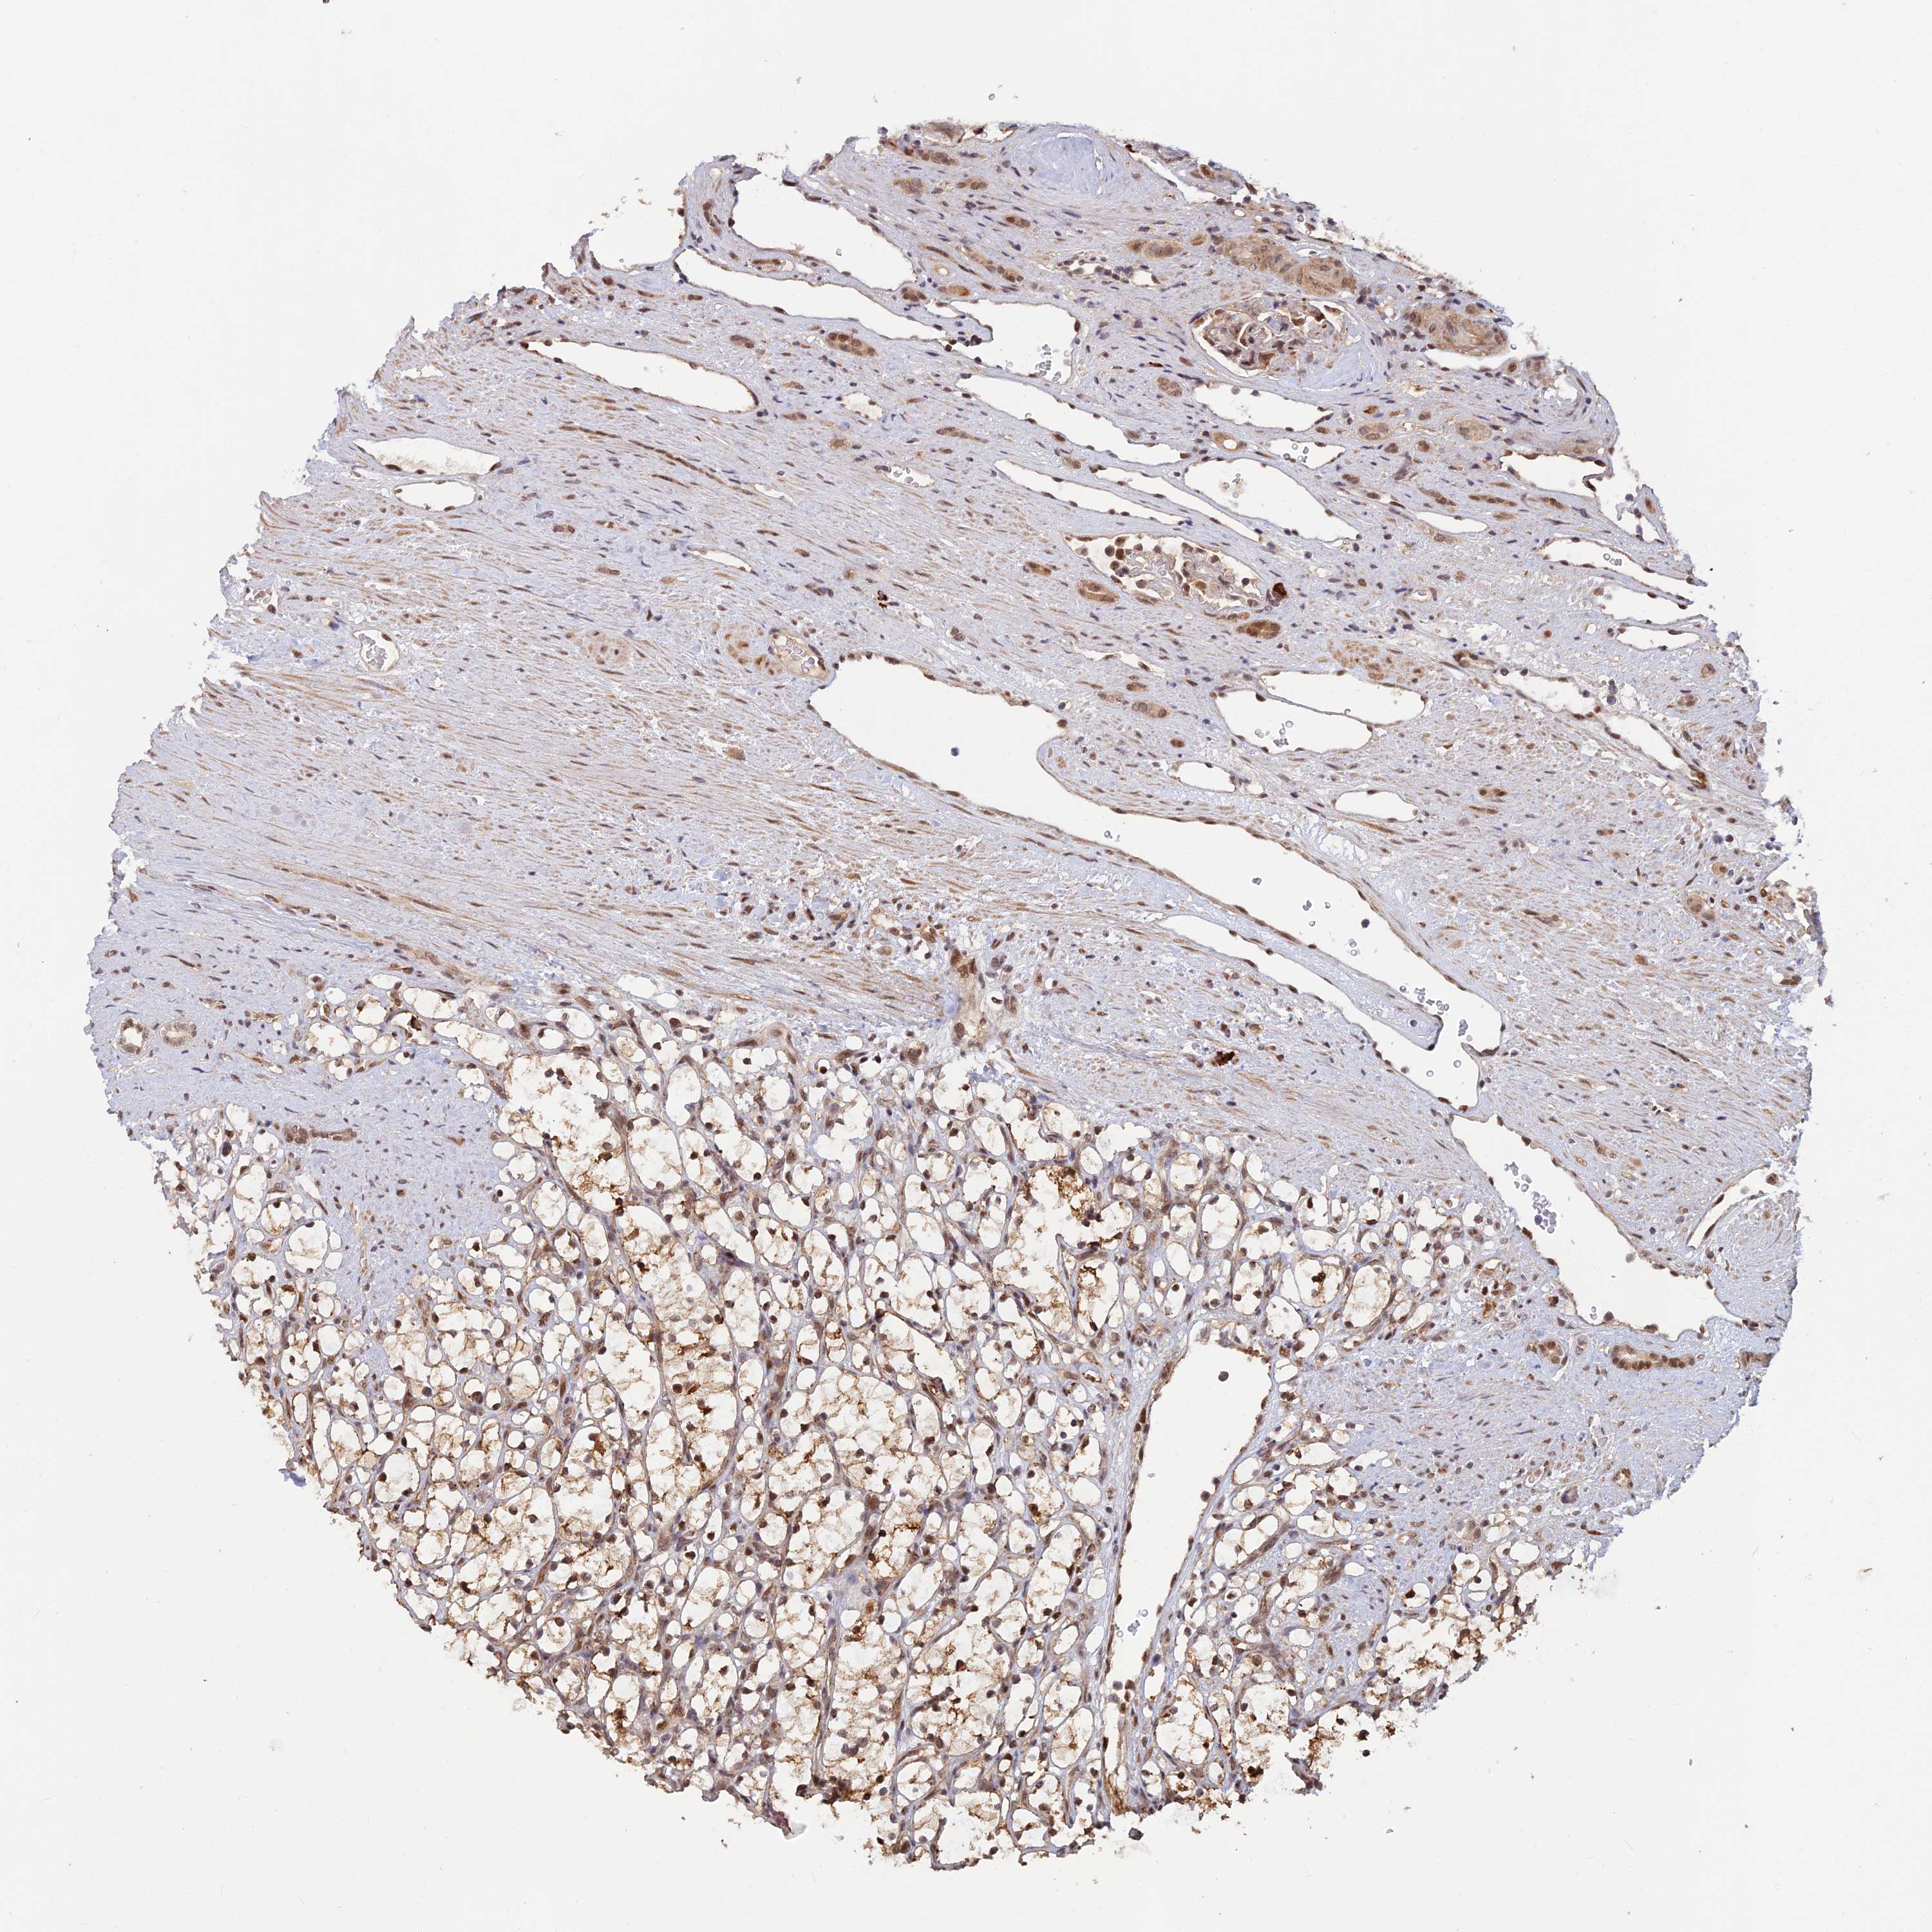

KIDNEY RENAL CLEAR CELL CARCINOMA (VALIDATION) - Interactive survival scatter ploti

The Survival Scatter plot shows the clinical status (i.e. dead or alive) for all individuals in the patient cohort, based on the same data that underlies the corresponding Kaplan-Meier plots. Patients that are alive at last time for follow-up are shown in blue and patients who have died during the study are shown in red.

The x-axis shows the expression levels (FPKM) of the investigated gene in the tumor tissue at the time of diagnosis. The y-axis shows the follow-up time after diagnosis (years). Both axes are complimented with kernel density curves demonstrating the data density over the axes. The top density plot shows the expression levels (FPKM) distribution among dead (red) and alive patients (blue). The right density plot shows the data density of the survived years of dead patients with high and low expression levels respectively, stratified using the cutoff indicated by the vertical dashed line through the Survival Scatter plot. This cutoff is automatically defined based on the FPKM cutoff that minimizes the p-score. The cutoff can be changed by dragging the vertical line or by entering a cutoff value in the square labeled "Current cut-off".

Under the Survival Scatter plot the p-score landscape (black curve; left axis) is shown together with dead median separation (red curve; right axis). Dead median separation is the difference in median mRNA expression between patients who have died with high and low expression, respectively. It is calculated as follows: median FPKM expression of dead patients with high expression - median FPKM expression of dead patients with low expression. This is intended to aid the user in visually exploring custom cutoffs and the associated p-scores and dead median separation.

Individual patient data is displayed and can be filtered by clicking on one or more of the category buttons on the top of the page. Categories describing expression level and patient information include: high, low, alive, dead, female, male and tumor stages. The scale of the x-axis can be toggled between linear and log-scale by clicking on the "x log" button. Mouse-over function shows TCGA ID, patient information and mRNA expression (FPKM) for each patient.

& Survival analysisi

Kaplan-Meier plots summarize results from analysis of correlation between mRNA expression level and patient survival. Patients were divided based on level of expression into one of the two groups "low" (under cut off) or "high" (over cut off). X-axis shows time for survival (years) and y-axis shows the probability of survival, where 1.0 corresponds to 100 percent.

ZNF565 is not prognostic in Kidney Renal Clear Cell Carcinoma (validation)

Best expression cut offi

Based on the FPKM value of each gene, patients were classified into two groups and association between prognosis (survival) and gene expression (FPKM) was examined. The best expression cut-off refers the FPKM value that yields maximal difference with regard to survival between the two groups at the lowest log-rank P-value. Best expression cut-off was selected based on survival analysis .

When clicking on this number, the vertical dashed line indicating cut-off, the interactive survival plot, and the Kaplan-Meier curve will be adjusted to show results based on the best expression cut-off.

: 2.91

Median expressioni

Median expression refers to the median FPKM value calculated based on the gene expression (FPKM) data from all patients in this dataset. When clicking on this number, the vertical dashed line indicating cut-off, the interactive survival plot, and the Kaplan-Meier curve will be adjusted to show results based on the median expression.

: N/A

P scorei

Log-rank P value for Kaplan-Meier plot showing results from analysis of correlation between mRNA expression level and patient survival.

N/A

5-year survival highi

5-year survival for patients with higher expression than the expression cutoff.

For melanoma and glioma, 3-year survival is shown.

5-year survival lowi

5-year survival for patients with lower expression than the expression cutoff.

TCGA RNA samplesi

RNA-seq data is reported as average FPKM (number Fragments Per Kilobase of exon per Million reads), generated by the The Cancer Genome Atlas (TCGA) .

Normal distribution across the dataset is visualized with box plots, shown as median and 25th and 75th percentiles. Points are displayed as outliers if they are above or below 1.5 times the interquartile range. FPKM values of the individual samples are presented next to the box plot.

Average pTPM 3.3

Number of samples 100